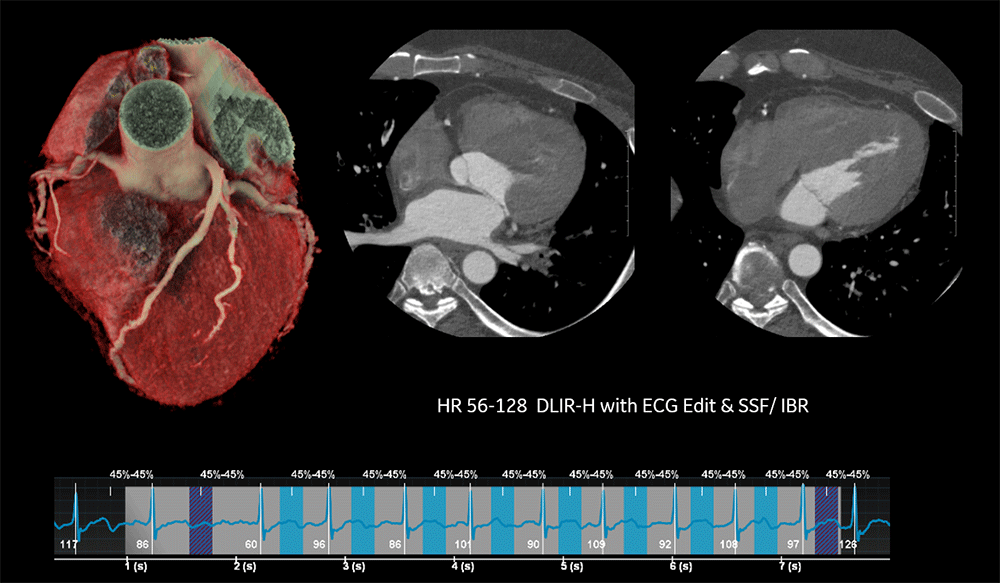

心臓撮影

Revolution Ascendで撮影した画像はSnapShot Freeze(冠動脈モーションアーチファクト低減機能)を使用することが可能であり、4cmカバレッジCTでありながら高心拍ならびに不整脈に対応した心臓撮影が可能である。ここではその1例となる画像を紹介する。

HR56-128の症例においても、GECTのCardiac Technologyである、SnapShot Freeze, ECG Editor, IBR (バンディングアーチファクト低減機能)を使用することで、短時間で画像処理が可能である。

Ascend_Toda_04.png